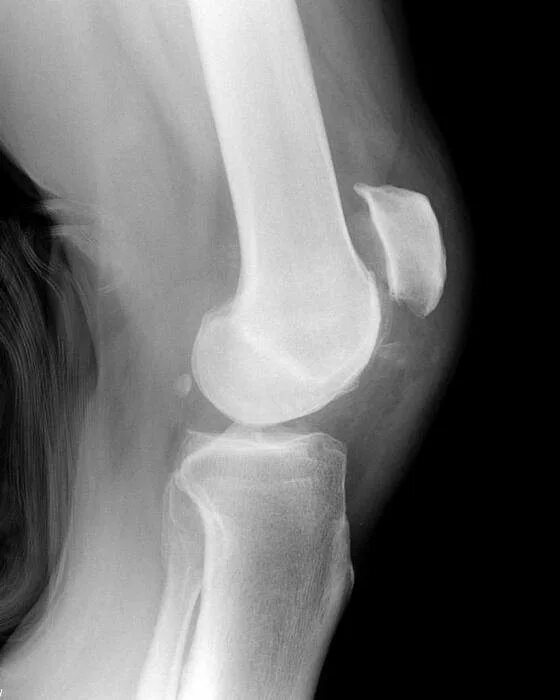

Смещение суставов вывих